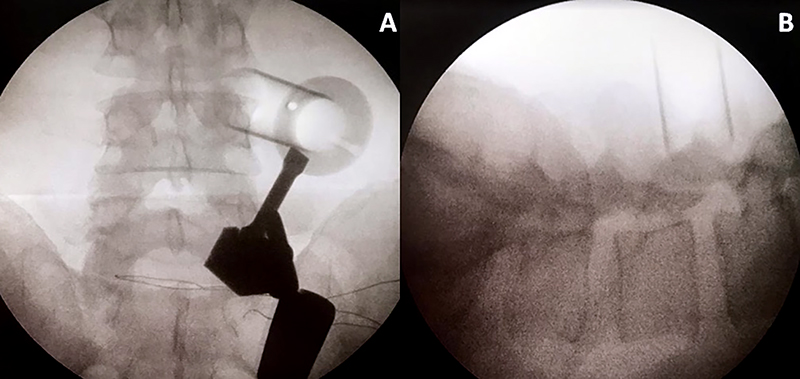

Todos los pacientes fueron operados bajo anestesia general y en decúbito prono con dos realces, uno a nivel torácico y el segundo en la pelvis. El brazo en C de radioscopia se coloca por debajo del paciente y el monitor se ubica los pies del mismo. El microscopio debe estar situado del lado opuesto al equipo de radioscopia. Se coloca un soporte en la barra lateral de la camilla, el cual sujetará posteriormente el brazo mecánico. Se realiza asepsia y colocación de campos estériles, con posterior localización del nivel a tratar con radioscopia. Realizamos una incisión paramediana de 2 cm. de largo, a 5 cm. lateral de la línea media. Luego se incide la fascia y se colocan los dilatadores correspondientes, para finalmente colocar un canal de trabajo de 20 mm. de diámetro (el largo dependerá de la contextura física de cada paciente). Se fija el canal de trabajo con el brazo mecánico cuando su ubicación se considera correcta.

El tubo debe dirigirse al espacio intertransverso del disco a tratar, teniendo como límites del espacio de trabajo, las apófisis transversas a nivel superior e inferior y las apófisis articulares medialmente. Esto se corrobora realizando radioscopia con incidencia anteroposterior y perfil (fig. 1).

Figura 1: Radioscopía intraoperatoria. Colocación del sistema tubular mínimamente invasivo.